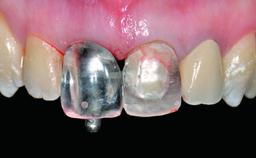

A 28-year-old patient presented at her general dentist’s office and complained about the appearance of her tooth 21. The patient had a history of trauma to this tooth. Endodontic treatment had been performed in the past and a crown placed on the tooth. A procedure to replace the old crown was performed by her dentist; however, a perforation on the middle third of the root occurred, and extraction of tooth 21 was suggested. Upon clinical and radiographic examination of the patient, who had been referred to us, replacement of tooth 21 by a dental implant appeared to be indicated.

Abutment Type Customized

Prosthesis Type FDP